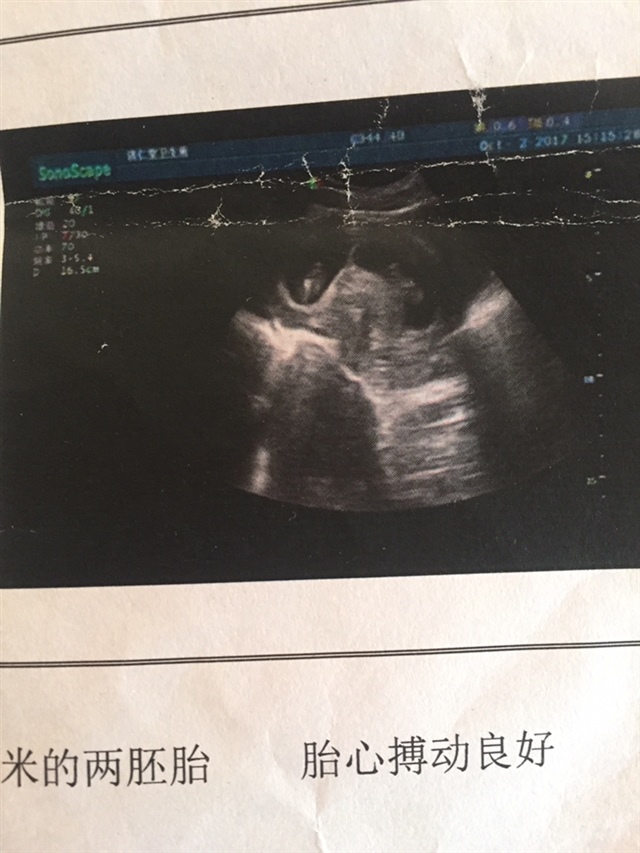

孕9周+6天

应该是双卵,我也是双的

孕9周+0天

两胚胎呀